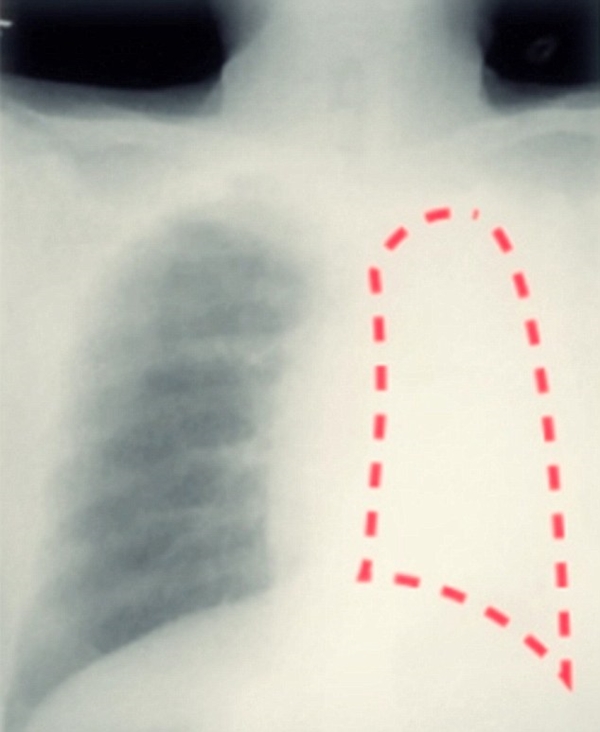

หลังจากผลเอกซ์เรย์ปรากฏออกว่าปอดซ้ายของเขาอันตรธานไปทั้งหมด ในทีแรกก็คิดว่าปอดซ้ายของเขาอาจจะถูกครอบงำด้วยเนื้องอกขนาดใหญ่ก็ได้ จึงทำการผ่าตัดไขปริศนา และเมื่อผ่าตัดแล้วก็ถึงบางอ้อเมื่อพบว่า ต้นตอของ "ปอดหาย" ไม่ใช่เนื้องอกอย่างที่คาดไว้ แต่เป็นปลอกปากกาเล็ก ๆ เข้าไปอุดตันหลอดลมที่เชื่อมไปยังปอดซ้าย จึงได้ถามไถ่นายหยู หัง ว่าเกิดอะไรขึ้นกับเขา ปลอกปากกาเข้าไปอยู่ในนั้นได้อย่างไร

ภาพจาก Sir Run Run Shaw Hospital School of Medicine